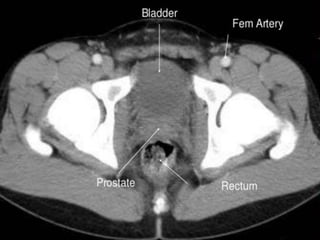

Urinary Bladder:

 The urinary bladder is covered superiorly by peritoneum.

 The body is a hollow muscular cavity.

 The neck is continuous with the urethra.

 The trigone is a smooth triangular area of mucosa located

internally at the base of the bladder.

 The base of the triangle is superior and bounded by the two

openings of the ureters.

 The apex of the trigone points inferiorly and is the opening for

the urethra.

CT cross sectional

anatomy.